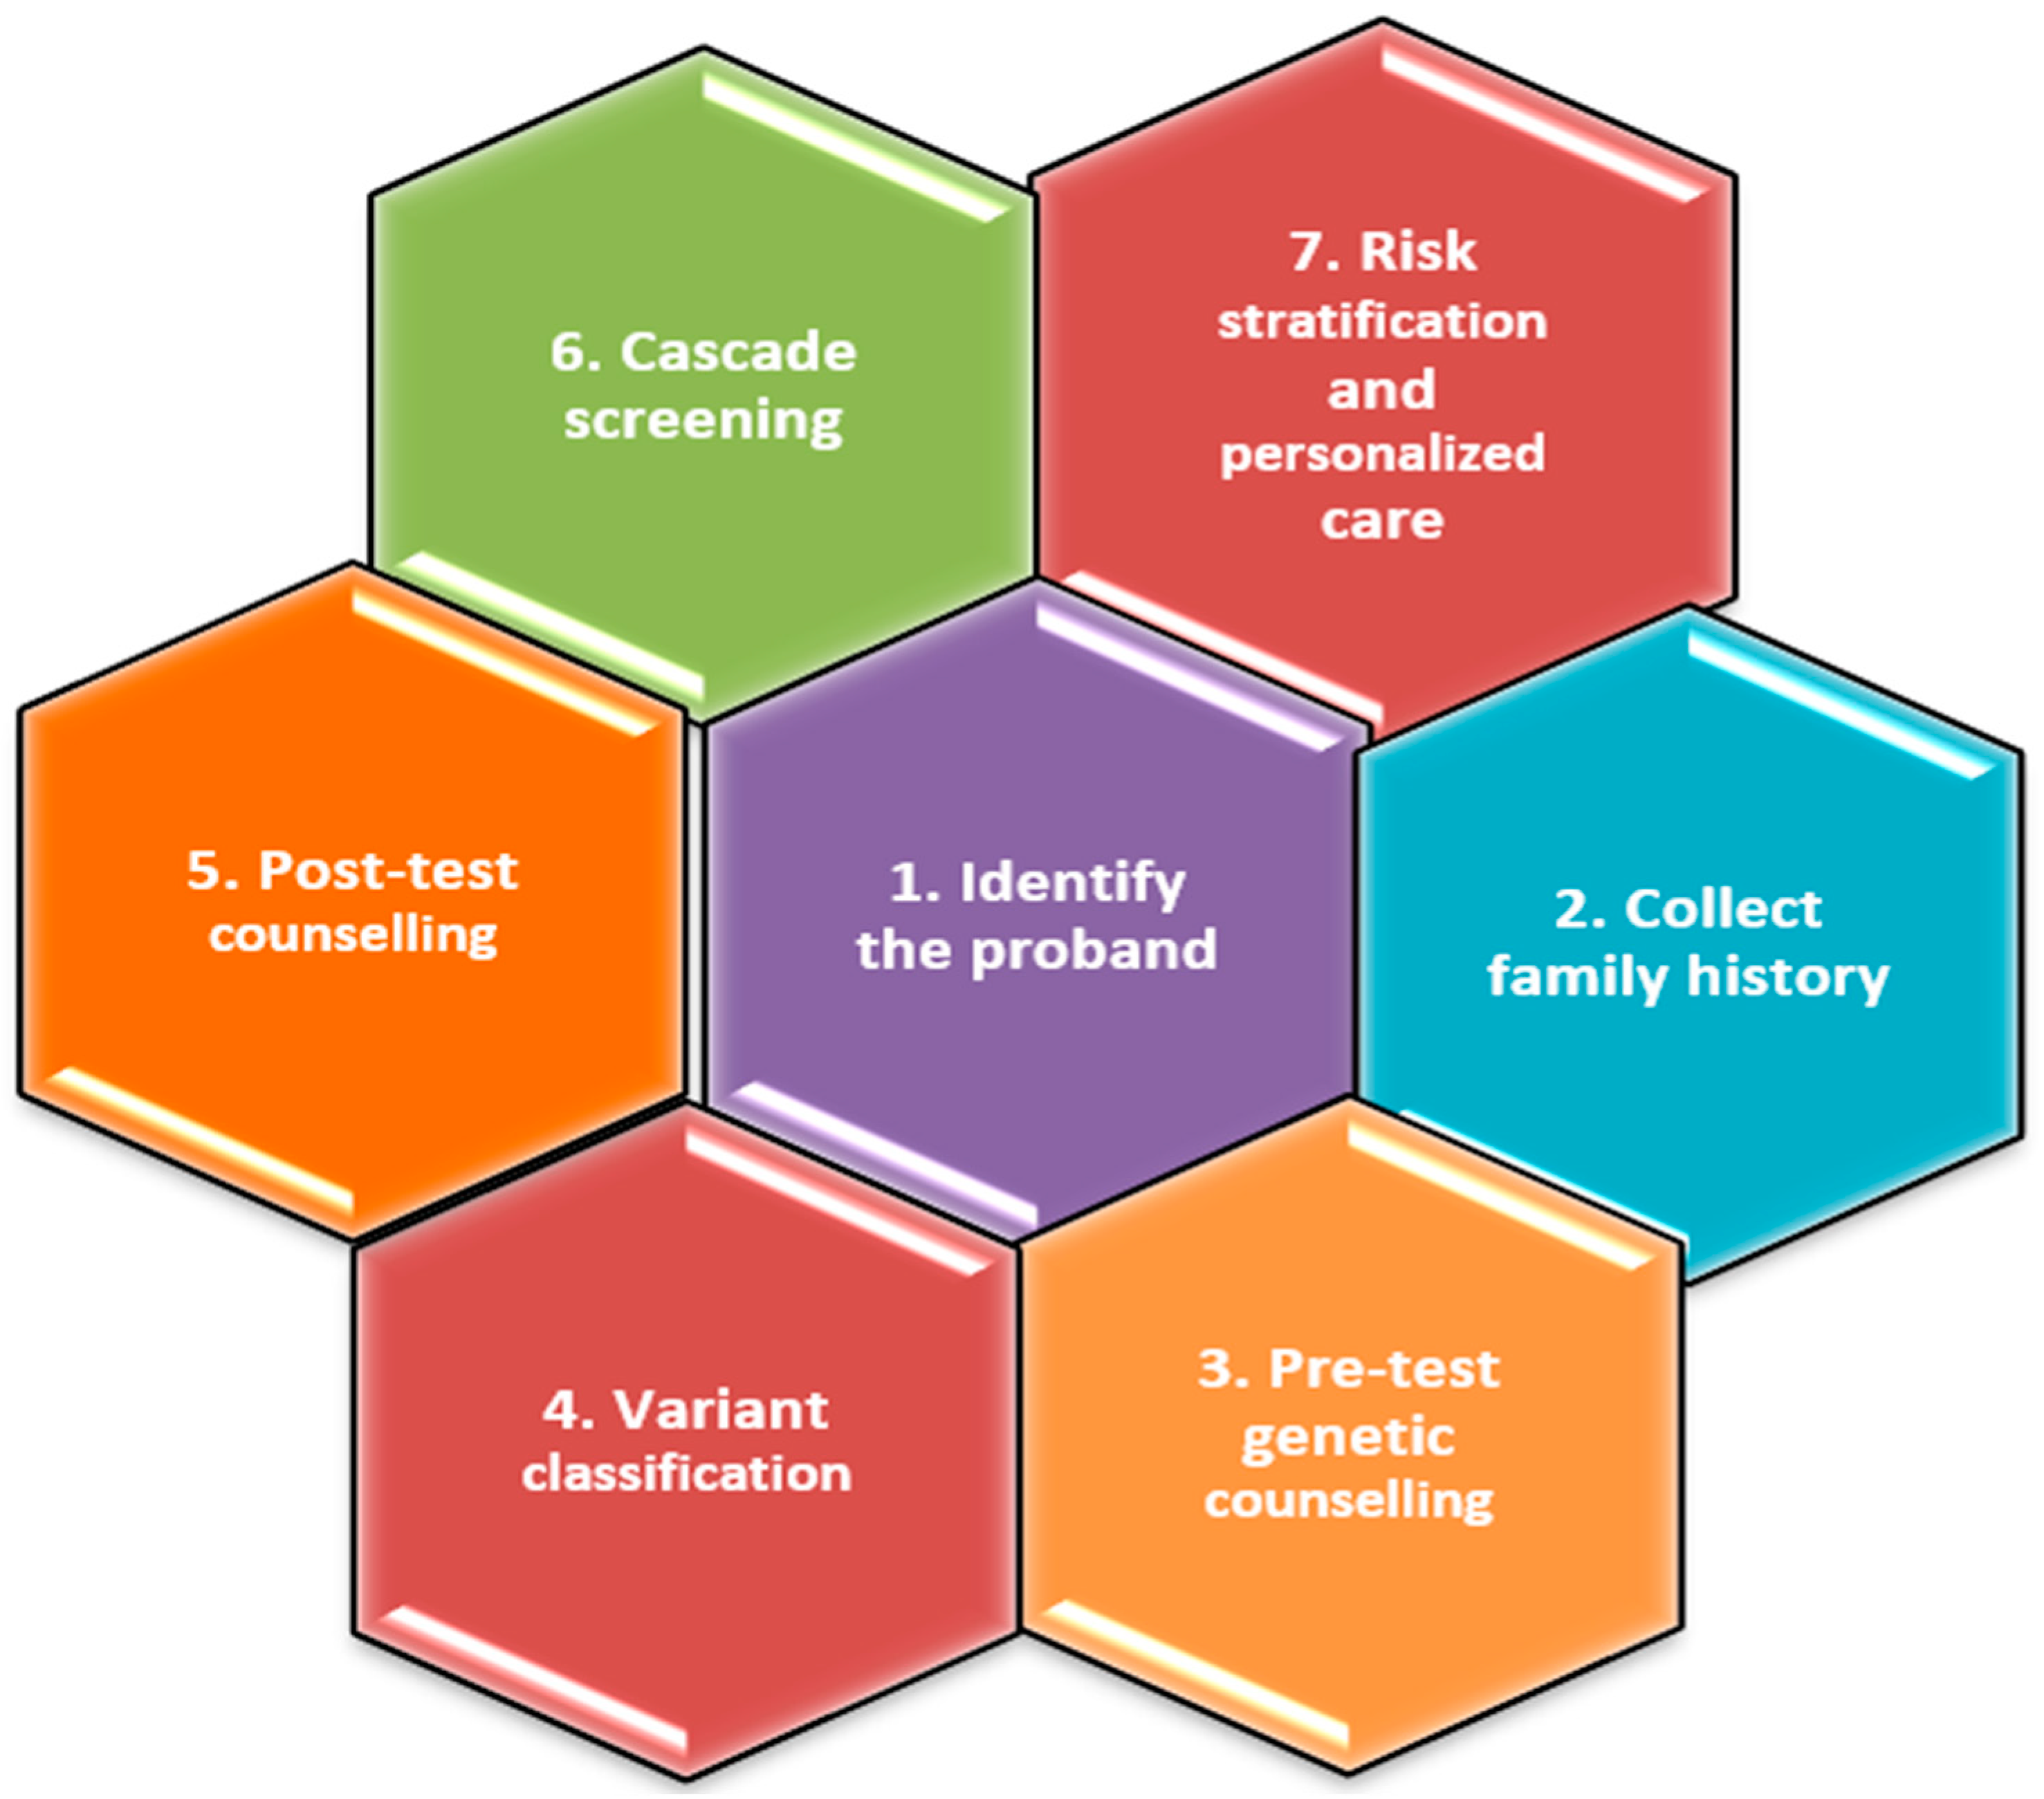

5. Genetic Testing

5.1. Benefits of Genetic Testing

5.2. Genetic Testing on the Proband

5.3. Prenatal Genetic Testing

5.4. Genetic Testing on the Relatives of the Proband